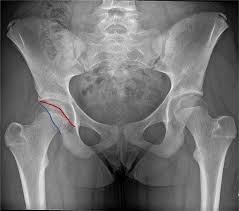

걸음걸이 변화와 절뚝거림

고관절 통증이 지속되면 자연스럽게 걸음걸이가 달라지는 경우가 많습니다.

• 한쪽 다리에 체중을 싣기 어려움

• 절뚝거리며 걷게 됨

• 보폭이 짧아짐

• 오래 걷기 힘들어짐

이러한 변화는 몸이 통증을 피하려는 보상 작용으로 나타나며, 장기적으로는 허리나 무릎 통증으로 이어질 수 있습니다.